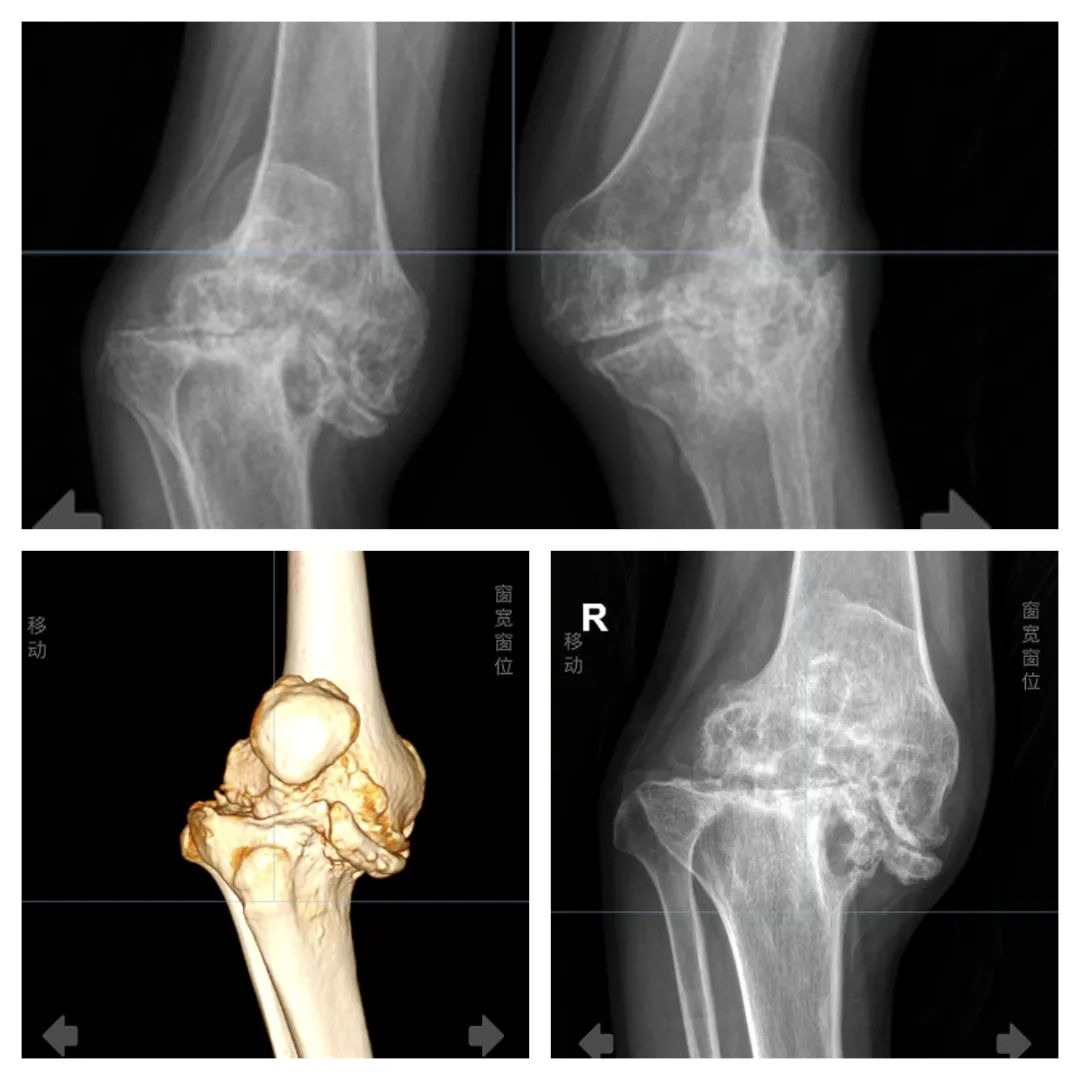

通过 X 线片和CT三维重建检查可以清晰的看到陈大哥的膝关节存在着 严重的变形及关节软骨病变,并伴有部分错位, 这是由于关节内的反复出血,导致慢性滑膜炎,进而破坏软骨导致关节间隙狭窄,关节僵硬,畸形。致使陈大哥即使在不行走的状态下也 时常感到关节疼痛,几乎不能自主行走, 严重的影响了生活质量。

术前三维重建、X 线片报告